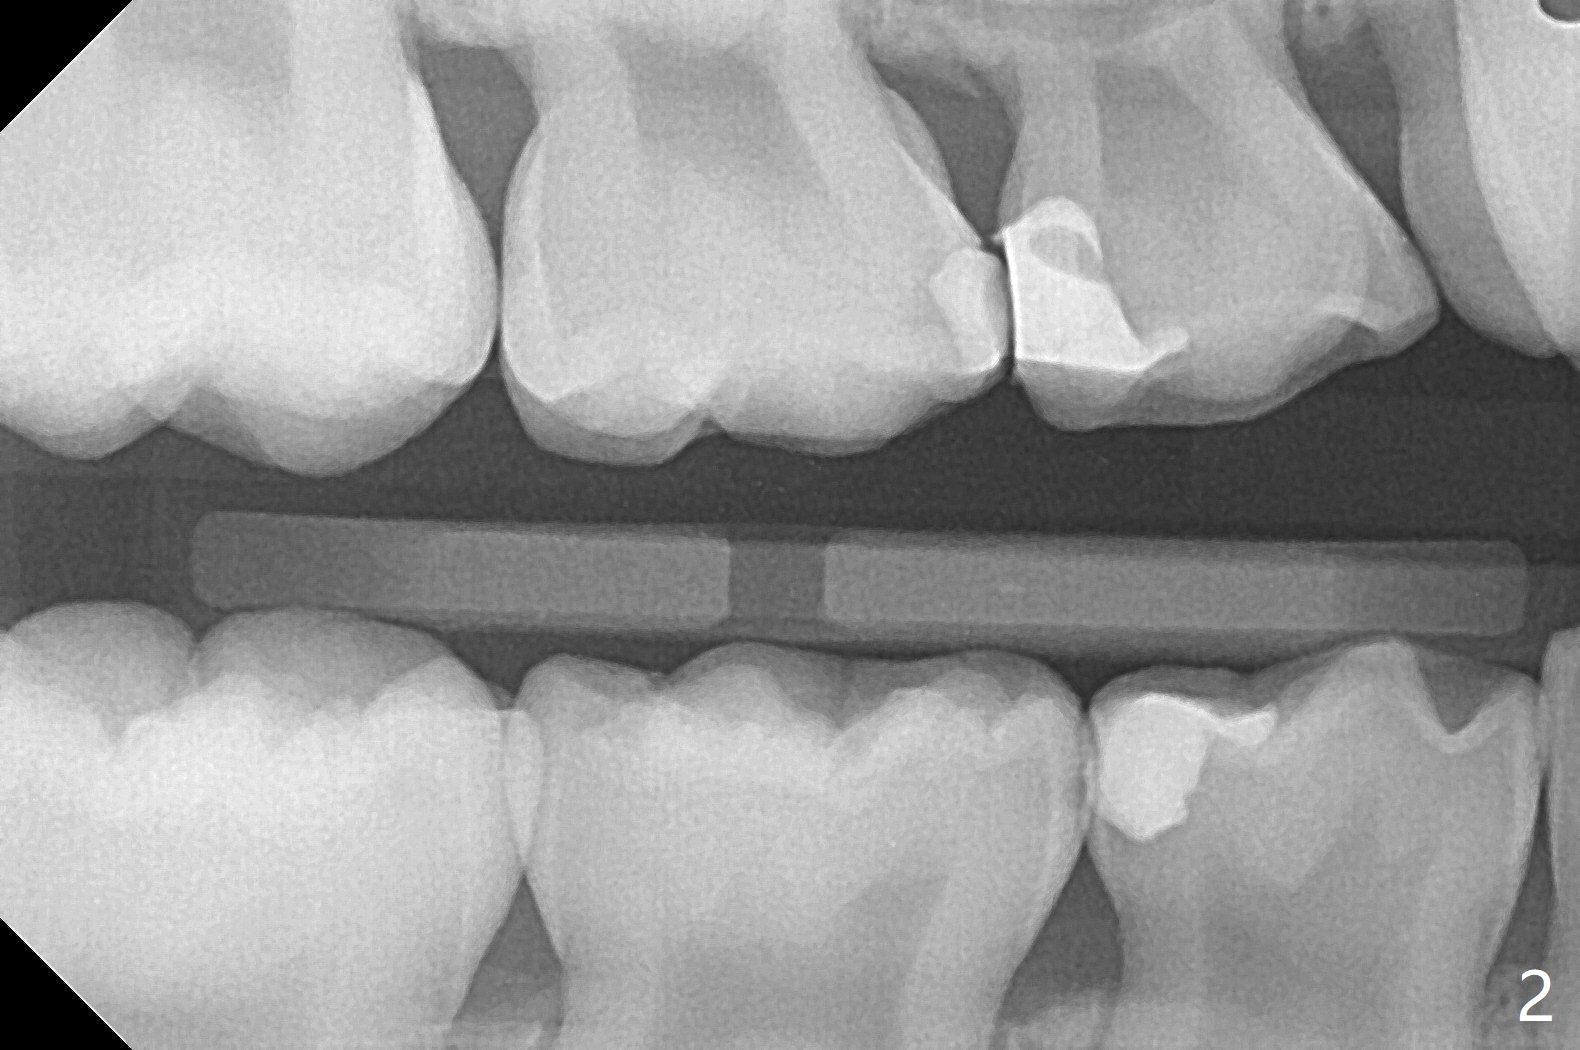

7岁女孩龋齿(图一)到八岁发展的严重(图二,三 (D))。为了有完整支抗,利用树脂(而不是不锈钢牙冠)保留左上第一乳磨牙(图六:D),以后可以安置矫正器。面部匀称(图七至十)。乳尖牙,第一恒磨牙:第一类咬合(图十一,十二)。左上前牙拥挤比右边轻,因为左上D龋齿破坏(图十三:D)。前牙扩弓时,右上D近中需要片切(^)。下颌拥挤轻(图十四),矫正器可以迟放置。